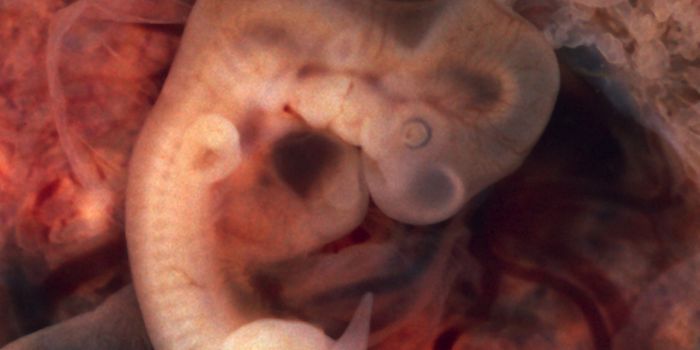

DEC 13, 2016CardiologyAs babies make the transition of depending on the mother for oxygen and depending on their own lungs during birth, an ar ...